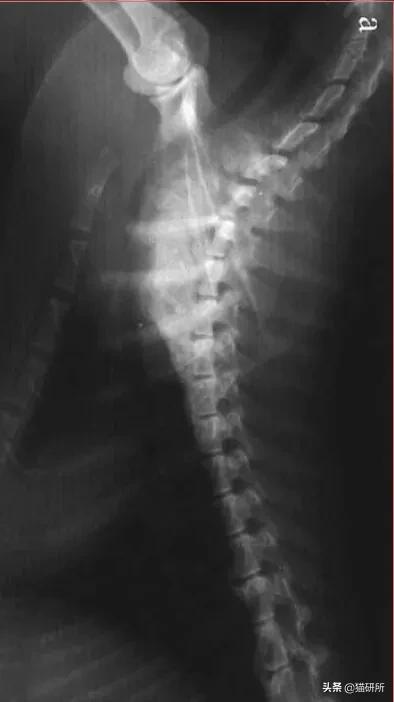

九岁去势公猫,长期以猪肝为主喂食自制食物。就诊时左前肢跛行,后出现霍纳氏综合征,两个月发展成瘫痪。

经病史检查,血液和影像学分析和以及血清维生素A浓度的测定,诊断为维生素A过量继发臂神经丛压迫。

尾颈椎和颅胸椎腹侧新骨形成